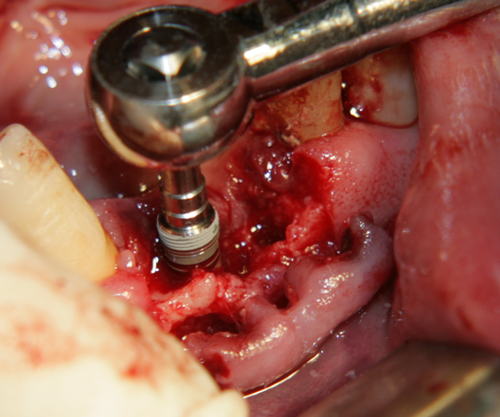

Имплантатът е поставен. За непрофесионалисти снимката е изключително зловеща - кръв, инструменти, зъби и нагледна човешка анатомия... В действителност обаче поставянето на зъбни импланти е една от най-атравматичните операции в областта на Оралната и Лицево - челюстната хирургия: не се отнема никакъв костен обем (както е при екстракцията на един ретиниран мъдрец например), поставя се стерилно тяло в костта, не се отпрепарират тъканите нашироко (както е при операцията на киста, остеомиелит или, недай боже, тумор). Изключително радко се налага антибиотичен прием постоперативно - обикновено при извършване на костна пластика в голям обем. Повече информация за приложението на антибиотиците в имплантологията прочетете тук...